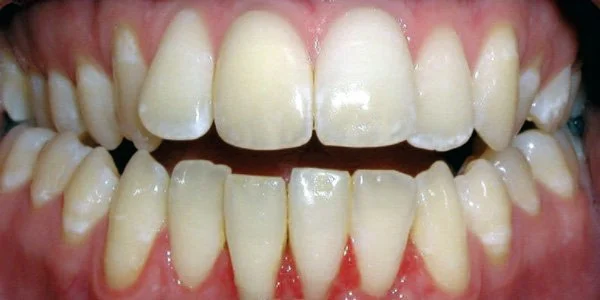

Protrusion

Upper teeth stick out beyond lower teeth